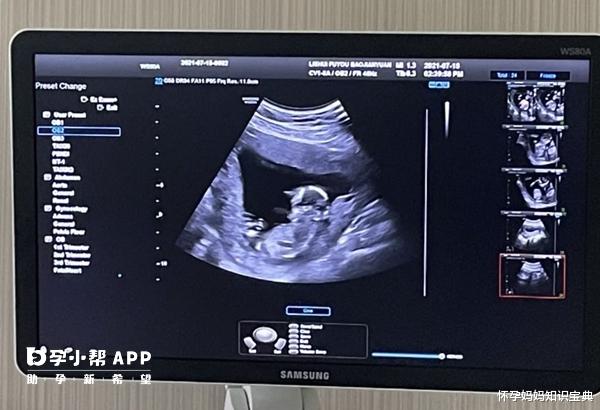

NT值2.4mm是男孩还是女孩NT主要是测量胎儿颈后透明层厚度,为早期产前筛查项目,通常在孕11到14周之间进行检查,而NT值2.4mm属于正常范围。一般NT<2.5mm都属于正常范围,NT值在2.5到3.0mm之间为临界风险,NT值>3.0mm则属于异常现象,如果NT值太高,那么就需要做羊水穿刺来确定胎儿是否有问题。大多孕妇在怀孕12后的时候就会做NT检查,因为这个是做的准确率最高,这些检查也是孕期的第一项排畸检查,不过网上有人宣称NT值大于1.5mm是怀的男孩,小于1mm是怀女孩,如果数值在1mm-1.5mm之间就是怀男怀女都有可能。

nt什么时候做是最佳时间?孕妇做NT检查的最佳时间是孕11-14周,胎儿偏小时NT不容易检测,胎儿偏大,随着淋巴回流到静脉,往往使NT值比实际偏小。NT检查由B超完成,是指B超检查时胎儿颈部皮肤层到皮下软组织的无回声区,正常值<3mm。NT值偏大提示染色体异常、先天性心脏病和大结构畸形,所以NT检测是孕早期发现胎儿畸形筛查的方法之一。